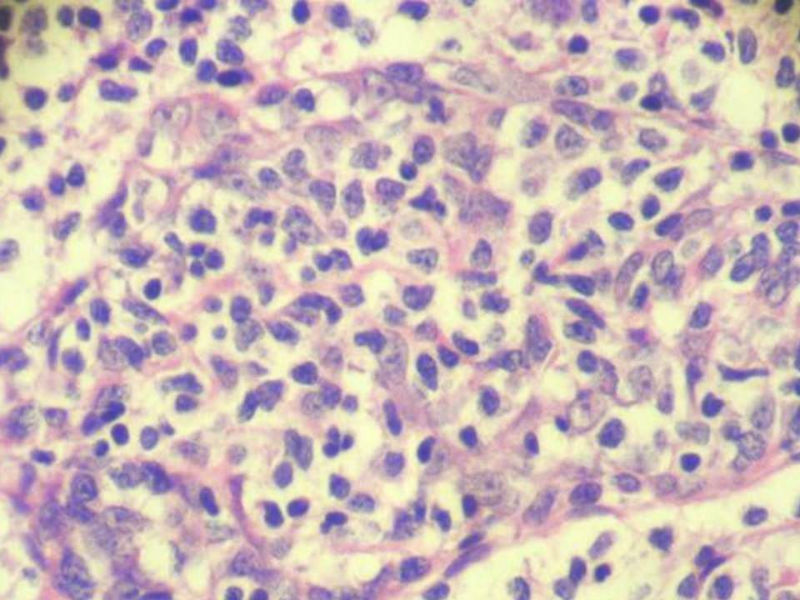

腮腺肿物:良性淋巴上皮病变(Mikulicz病)

女,71岁,腮腺肿物,临床诊断混合瘤。

增生的上皮样细胞团怎么有些像血管内皮呢,不够清晰。